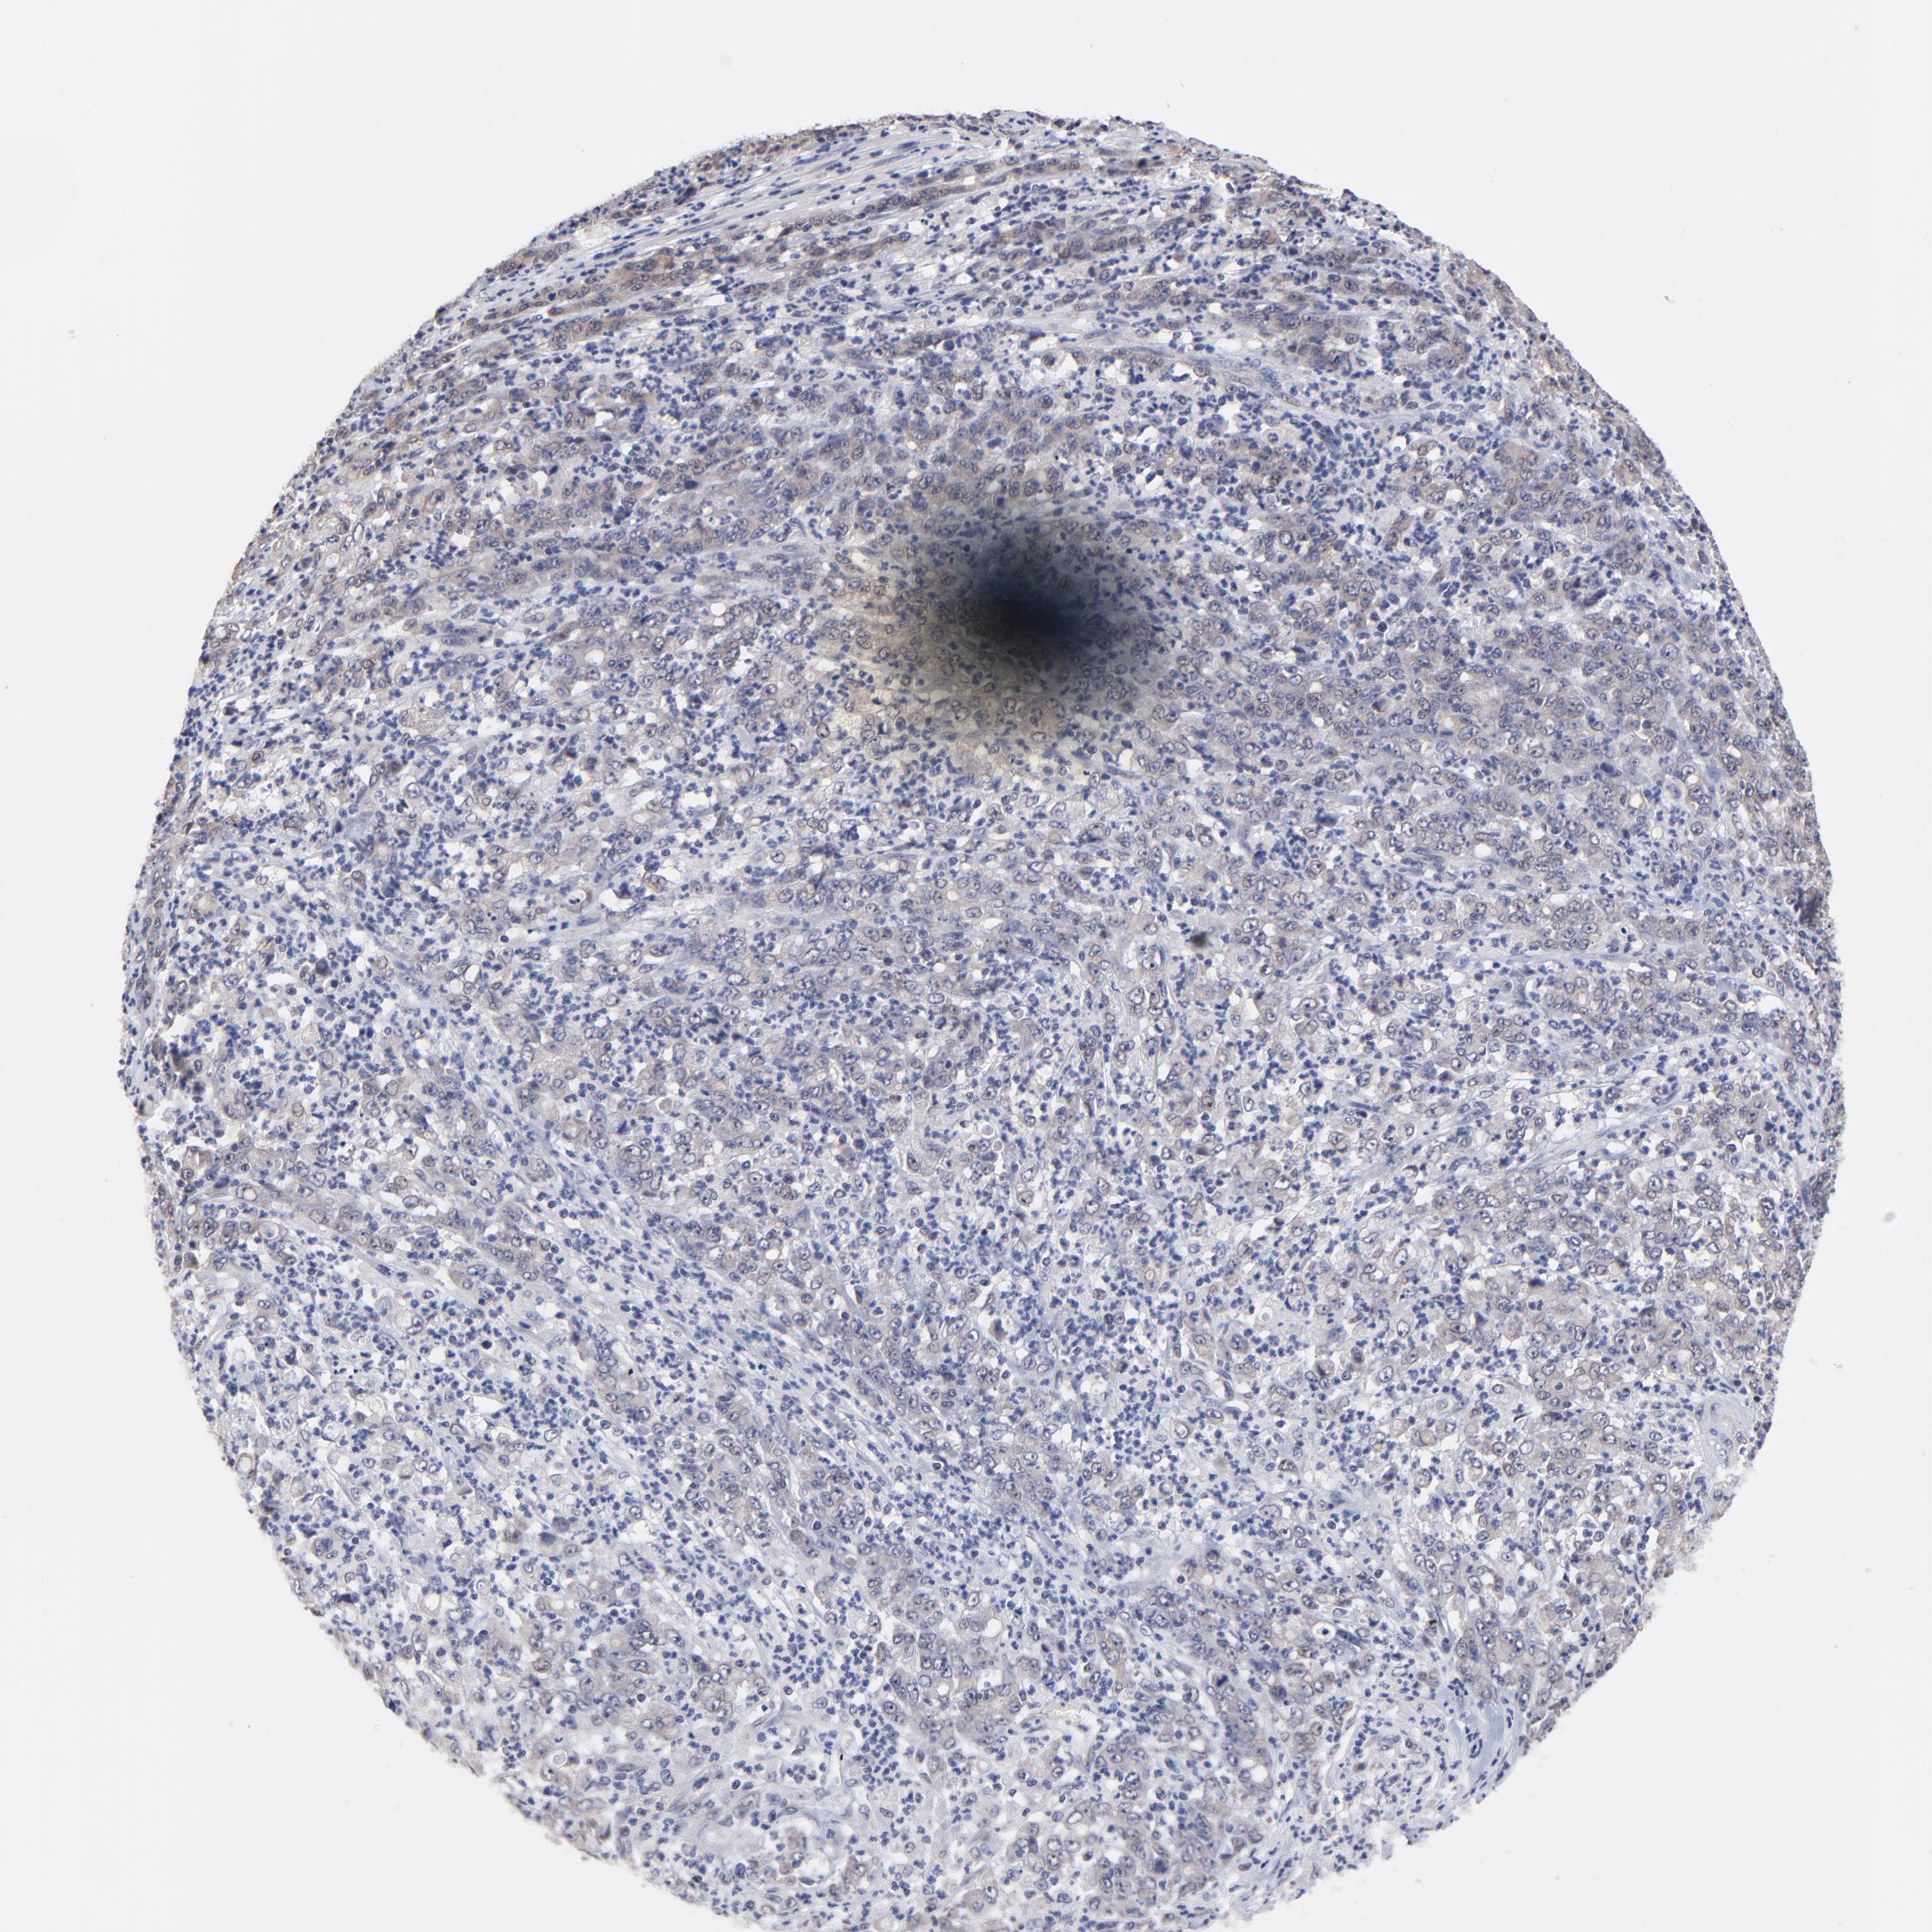

STOMACH CANCER - Protein expressioni

A mouse-over function shows sample information and annotation data. Click on an image to view it in a full screen mode. Samples can be filtered based on level of antibody staining by selecting one or several of the following categories: high, medium, low and not detected. The assay and annotation is described here.

Note that samples used for immunohistochemistry by the Human Protein Atlas do not correspond to samples in the TCGA dataset.

Antibody stainingi

Antibody staining in the annotated cell types in the current human tissue is reported as not detected, low, medium, or high, based on conventional immunohistochemistry profiling in selected tissues. This score is based on the combination of the staining intensity and fraction of stained cells.

Each image is clickable and will lead to virtual microscopy that enables deeper exploration of all samples and also displays staining intensity scores, fraction scores and subcellular localization as well as patient and tissue information for each sample.

Antibody HPA002885

Staining

High

Medium

Low

Not detected

Intensity

Strong

Moderate

Weak

Negative

Quantity

>75%

75%-25%

<25%

None

Location

Nuclear

Cytoplasmic/membranous

Cytoplasmic/membranous,nuclear

Adenocarcinoma, NOS

Adenocarcinoma, High grade